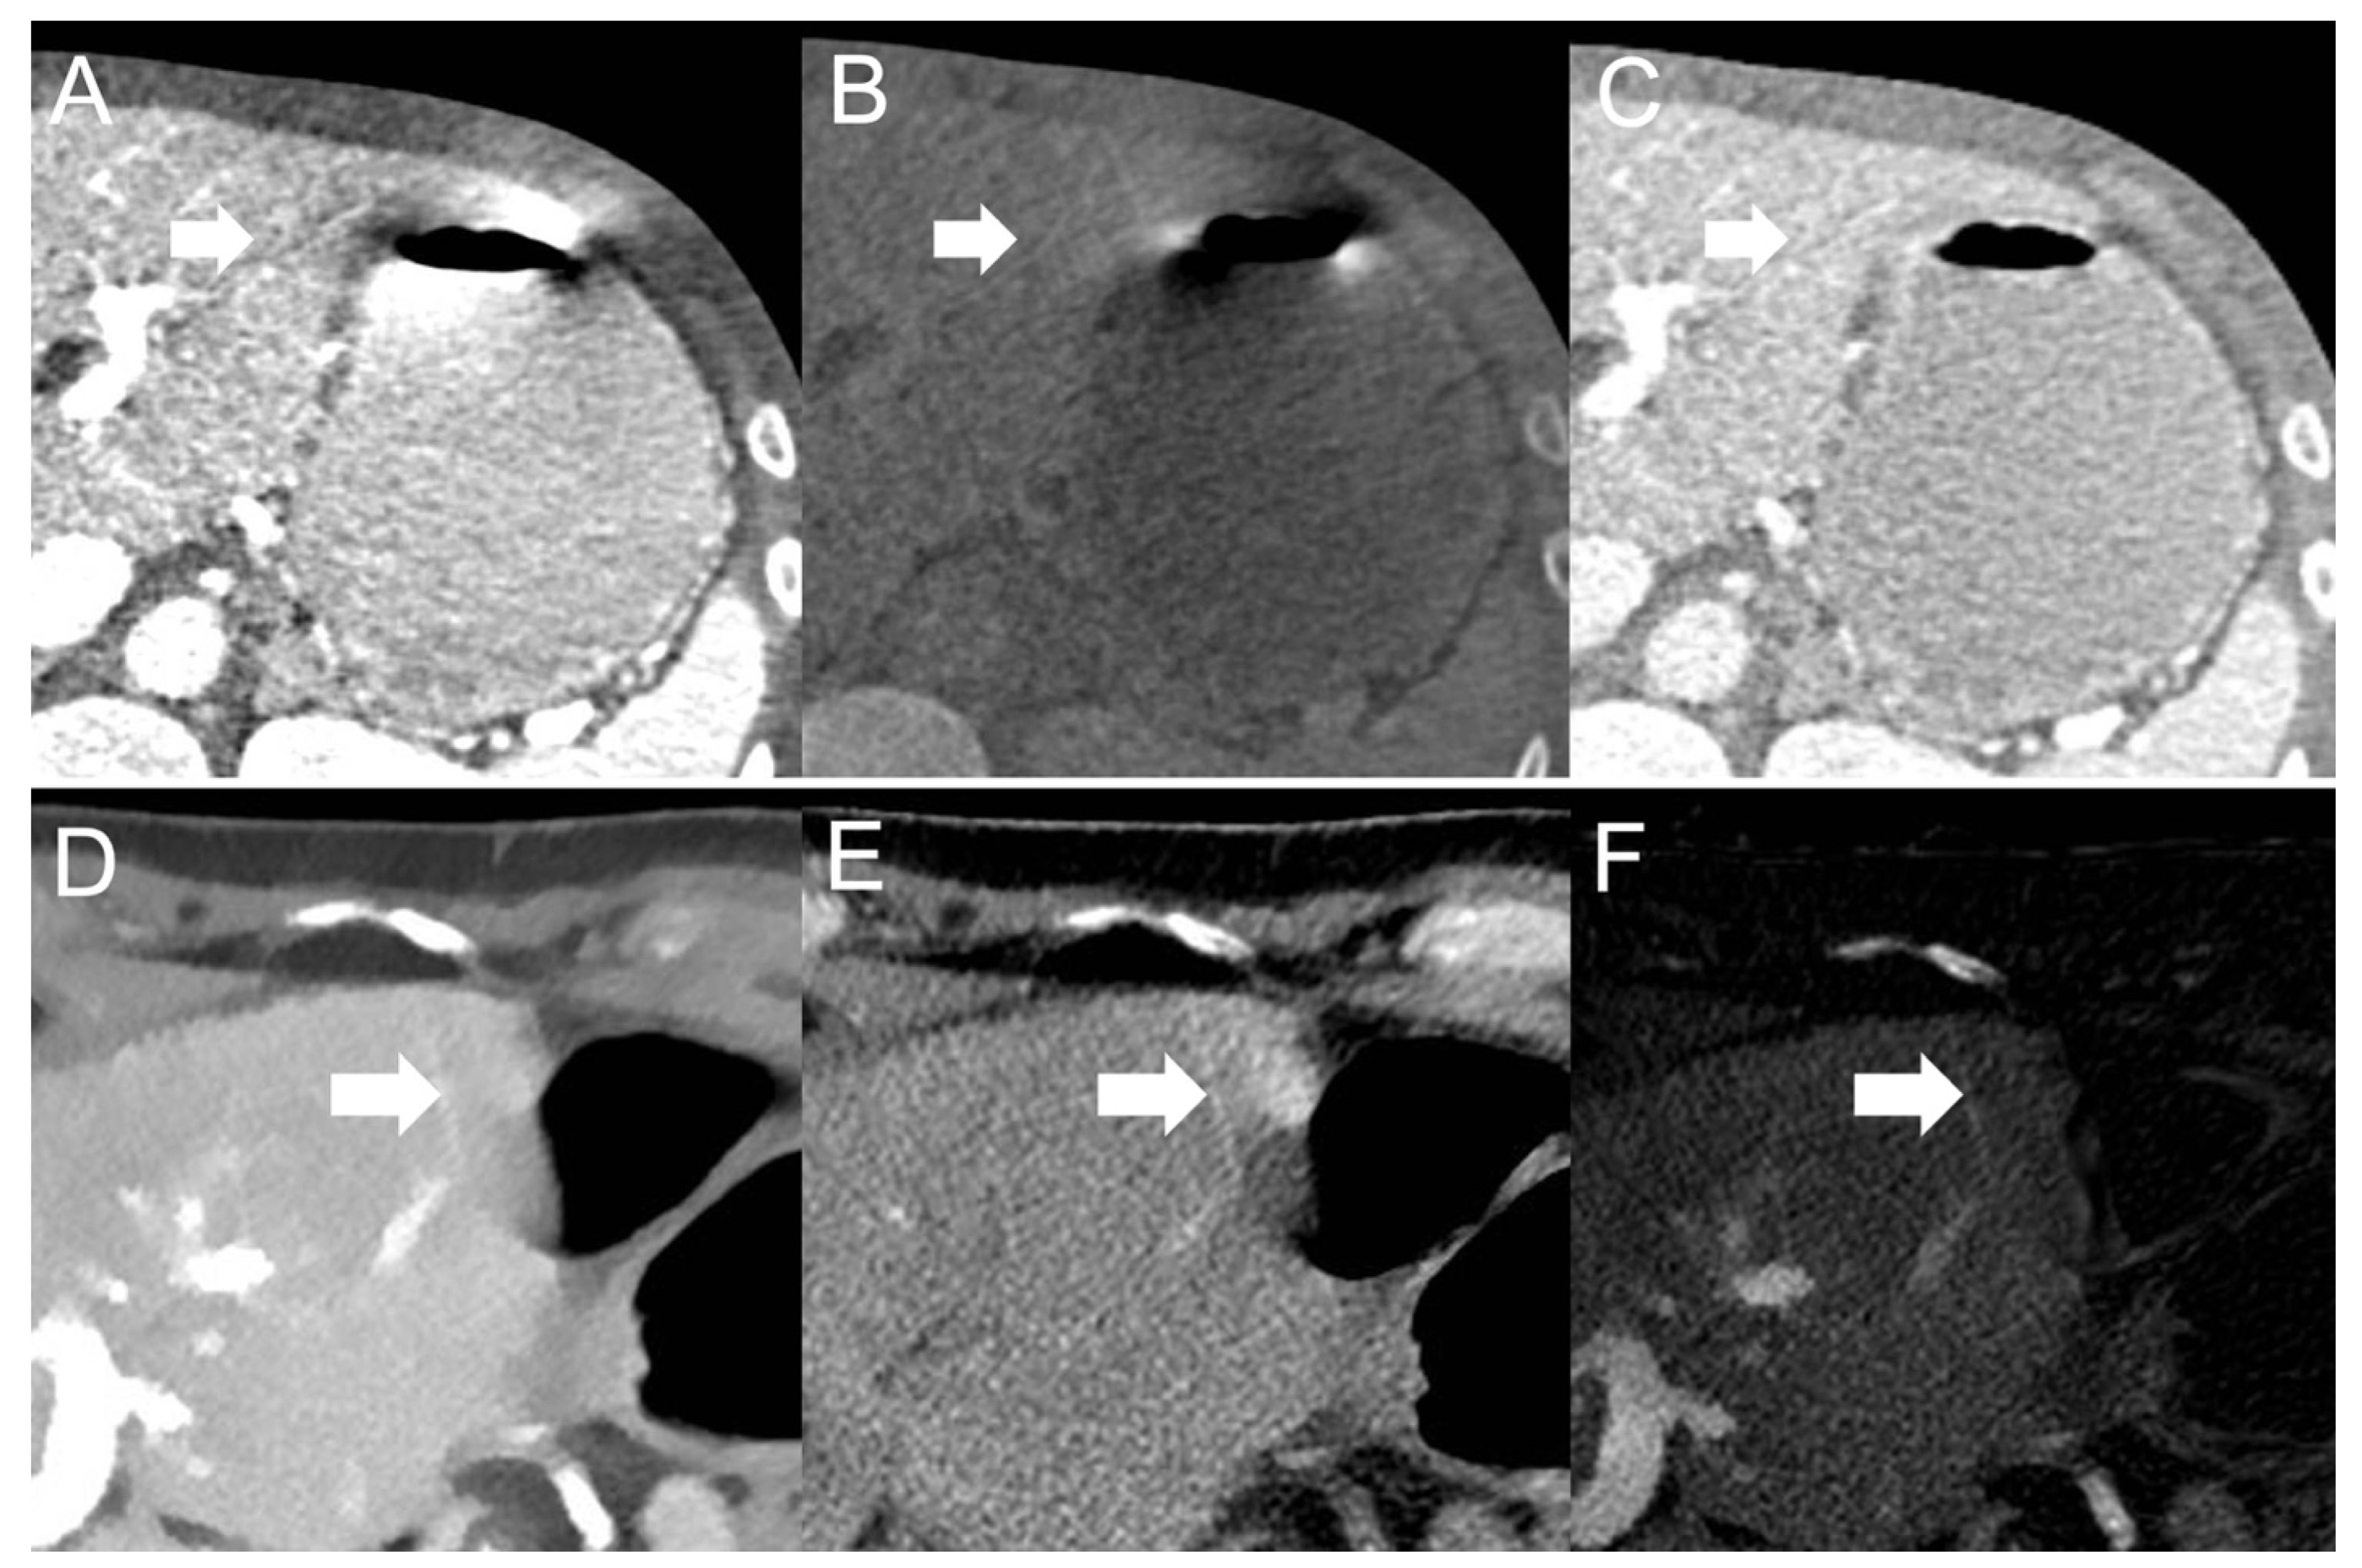

- Dual-source scanner: Depth of extension of visceral-motion-related artifacts into the liver (see Figure 2 and Figure 3) was significantly shorter (p < 0.001, each) for 120-kVp-like images (mean length: 5 ± 6 mm) compared with 40-keV (mean length: 16 ± 11 mm), 190-keV (mean length: 16 ± 9 mm), VNC (mean length: 15 ± 10 mm), and iodine (mean length: 16 ± 11 mm) images. Mean ROI measurements (HU or iodine concentration, respectively) were significantly different in the bright and dark artifact components compared to the neighboring liver parenchyma not affected by artifacts in 40-keV (p < 0.001, each), 190-keV (p < 0.001, each), VNC (p < 0.001, each), and iodine images (p < 0.001, each). However, in 120-kVp-like images, mean ROI measurements were not significantly different in bright (ROImin) artifact components compared to unaffected liver parenchyma (p = 0.32), as opposed to dark (ROImax) artifact components (p < 0.001).

- Twin-beam scanner: Depth of extension of visceral-motion-related artifacts into the liver was significantly shorter (p < 0.001, each) for 120-kVp-like images (mean length: 4 ± 5 mm) compared with 40-keV (mean length: 18 ± 12 mm), 190-keV (mean length: 16 ± 11 mm), VNC (mean length: 15 ± 11 mm), and iodine (mean length: 16 ± 11 mm) images. Mean ROI measurements were significantly different in the bright and dark artifact components compared to unaffected liver parenchyma in 120-kVp-like (p = 0.006, p = 0.03), 40-keV (p < 0.001, each), 190-keV (p < 0.001, each), VNC (p < 0.001, each), and iodine images (p < 0.001, each).

- Fast kV-switching scanner: Depth of extension of visceral-motion-related artifacts into the liver was significantly shorter (p < 0.001, each) for iodine (mean length: 6 ± 7 mm) images compared with 120-kVp-like (mean length: 11 ± 7 mm), 40-keV (mean length: 9 ± 8 mm), 140-keV (mean length: 10 ± 8 mm), and VNC (mean length: 13 ± 8 mm) images. Mean ROI measurements were significantly different in the bright and dark artifact components compared to unaffected liver parenchyma in 120-kVp-like (p < 0.001, each), 40-keV (p < 0.001, each), 140-keV (p < 0.001, each), VNC (p < 0.001, each), and iodine images (p < 0.001, each).

- Dual-layer spectral detector scanner: Depth of extension of visceral-motion-related artifacts into the liver was significantly shorter (p < 0.001, each) for iodine (mean length: 2 ± 5 mm) images compared with 120-kVp (mean length: 11 ± 5 mm), 40-keV (mean length: 10 ± 6 mm), 200-keV (mean length: 11 ± 5 mm), and VNC (mean length: 11 ± 5 mm) images. Mean ROI measurements were significantly different in the bright and dark artifact components compared to unaffected liver parenchyma in 120-kVp (p < 0.001, each), 40-keV (p < 0.001, each), 200-keV (p < 0.001, each), and VNC (p < 0.001, each) images. However, in iodine images mean ROI measurements were not significantly different in bright (ROImax) artifact components compared to unaffected liver parenchyma (p = 0.15), as opposed to dark (ROImin) artifact components (p < 0.001). Further details on quantitative artifact measurements are provided in Table 2 and the Supplementary Material.

- Dual-source scanner: Qualitative artifact scores (see Figure 4) were significantly lower (p < 0.001, each) for 120-kVp-like images (median score: 2, range: 1–5) compared with 40-keV (median score: 4, range: 1–5), 190-keV (median score: 3, range: 2–5), VNC (median score: 3, range: 2–5), and iodine (median score: 4, range: 1–5) images.

- Twin-bean scanner: Qualitative artifact scores were significantly lower (p < 0.001, each) for 120-kVp-like images (median score: 2, range: 1–4) compared with 40-keV (median score: 5, range: 1–5), 190-keV (median score: 3, range: 2–5), VNC (median score: 3, range: 1–5), and iodine (median score: 4, range: 1–5) images.

- Fast kV-switching scanner: Qualitative artifact scores were significantly lower (p < 0.001, each) for iodine images (median score: 2, range: 1–5) compared with 120-kVp-like (median score: 3, range: 1–5), 40-keV (median score: 3, range: 1–5), 140-keV (median score: 3, range: 1–5), and VNC (median score: 3, range: 1–5) images.

- Dual-layer spectral detector scanner: Qualitative artifact scores were significantly lower (p < 0.001, each) for iodine images (median score: 1, range: 1–3) compared with 120-kVp (median score: 3, range: 1–5), 40-keV (median score: 3, range: 1–5), 200-keV (median score: 3, range: 2–5), and VNC (median score: 3, range: 1–5) images. Further details on qualitative artifact scores are provided in the Supplementary Material.